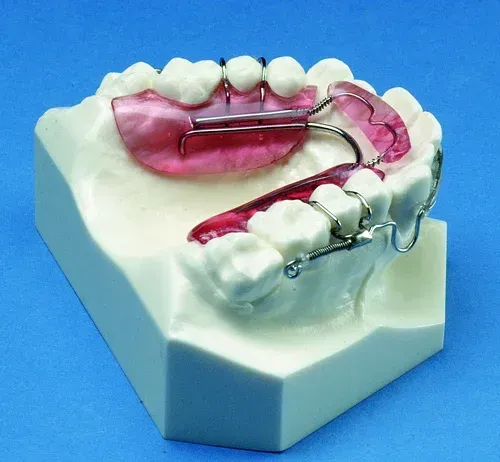

Other types of orthodontic appliances may also be used during the course of treatment. Some of these appliances are removable and can be taken in and out of the mouth, while others will be attached to the teeth until they are no longer needed.

Depending upon the specific needs of the case, these appliances may be used to accomplish a number of things including:

- Widening the jaws to make sufficient space for permanent teeth

- Influencing jaw growth

- The reduction of deep overbites

- Allowing the correction of teeth in crossbite

- Maintaining the space for a permanent tooth when a baby tooth has been prematurely lost

- Minor tooth movement

- Helping to control harmful oral habits